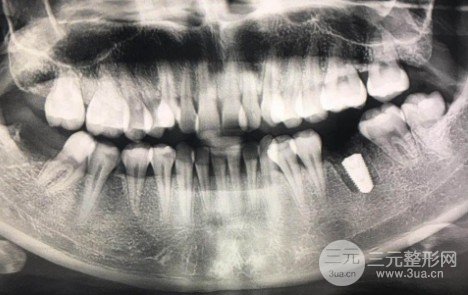

Dental implant case show